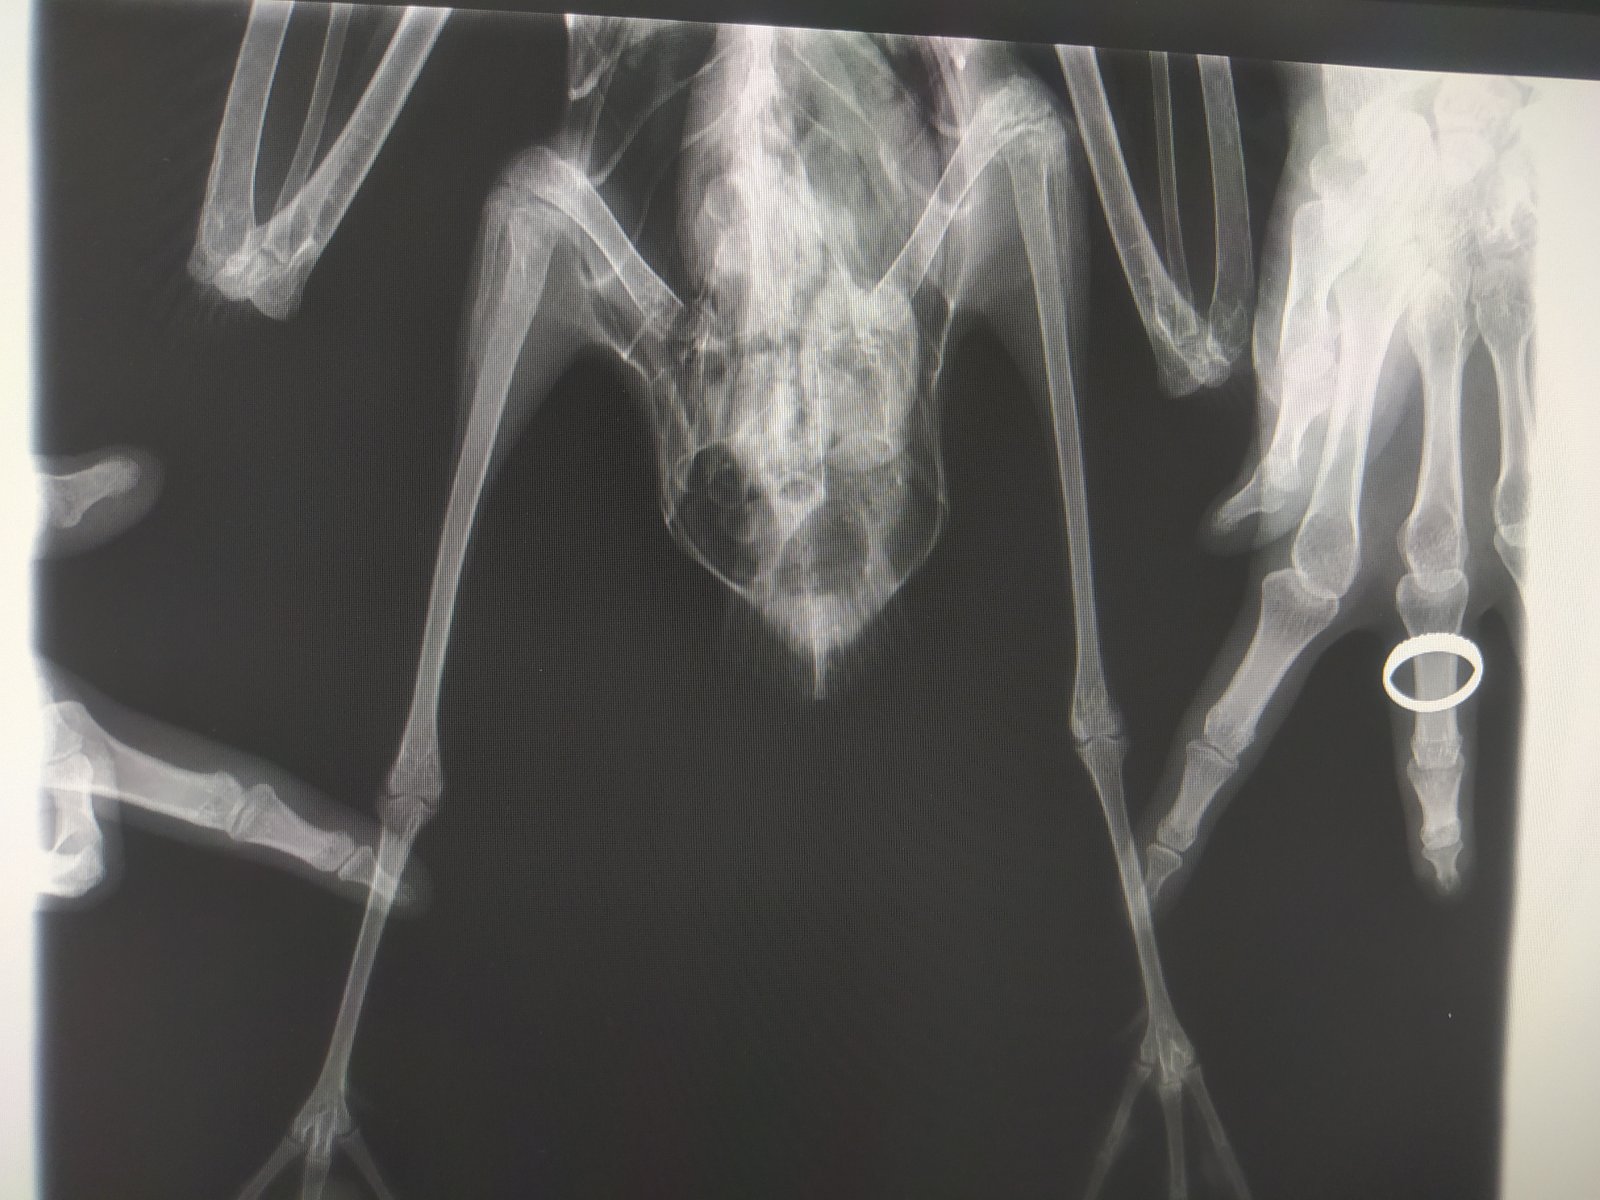

Четрые дня назад на участке нашла птицу, убегает, клюется, самостоятельно ест и пьет. В первый день была покормлена 2 варёными яйцами, все остальные дни только размороженная рыба. Днём гуляет по участку, на ночь убираю в картонную коробку. Думаю это серебристая или средиземноморская чайка. Вес около двух кг. На рентгене переломов не замечено

Короче, с костями птицы все было нормально, оба крыла рабочие, но.. Вот эта вот крохотная металлическая проволока проигнорированная мной на рентгене как артефакт её и убила(

Распорот кишечник, гнойный перетонит, тромб в сердце (скорее всего посмертный)